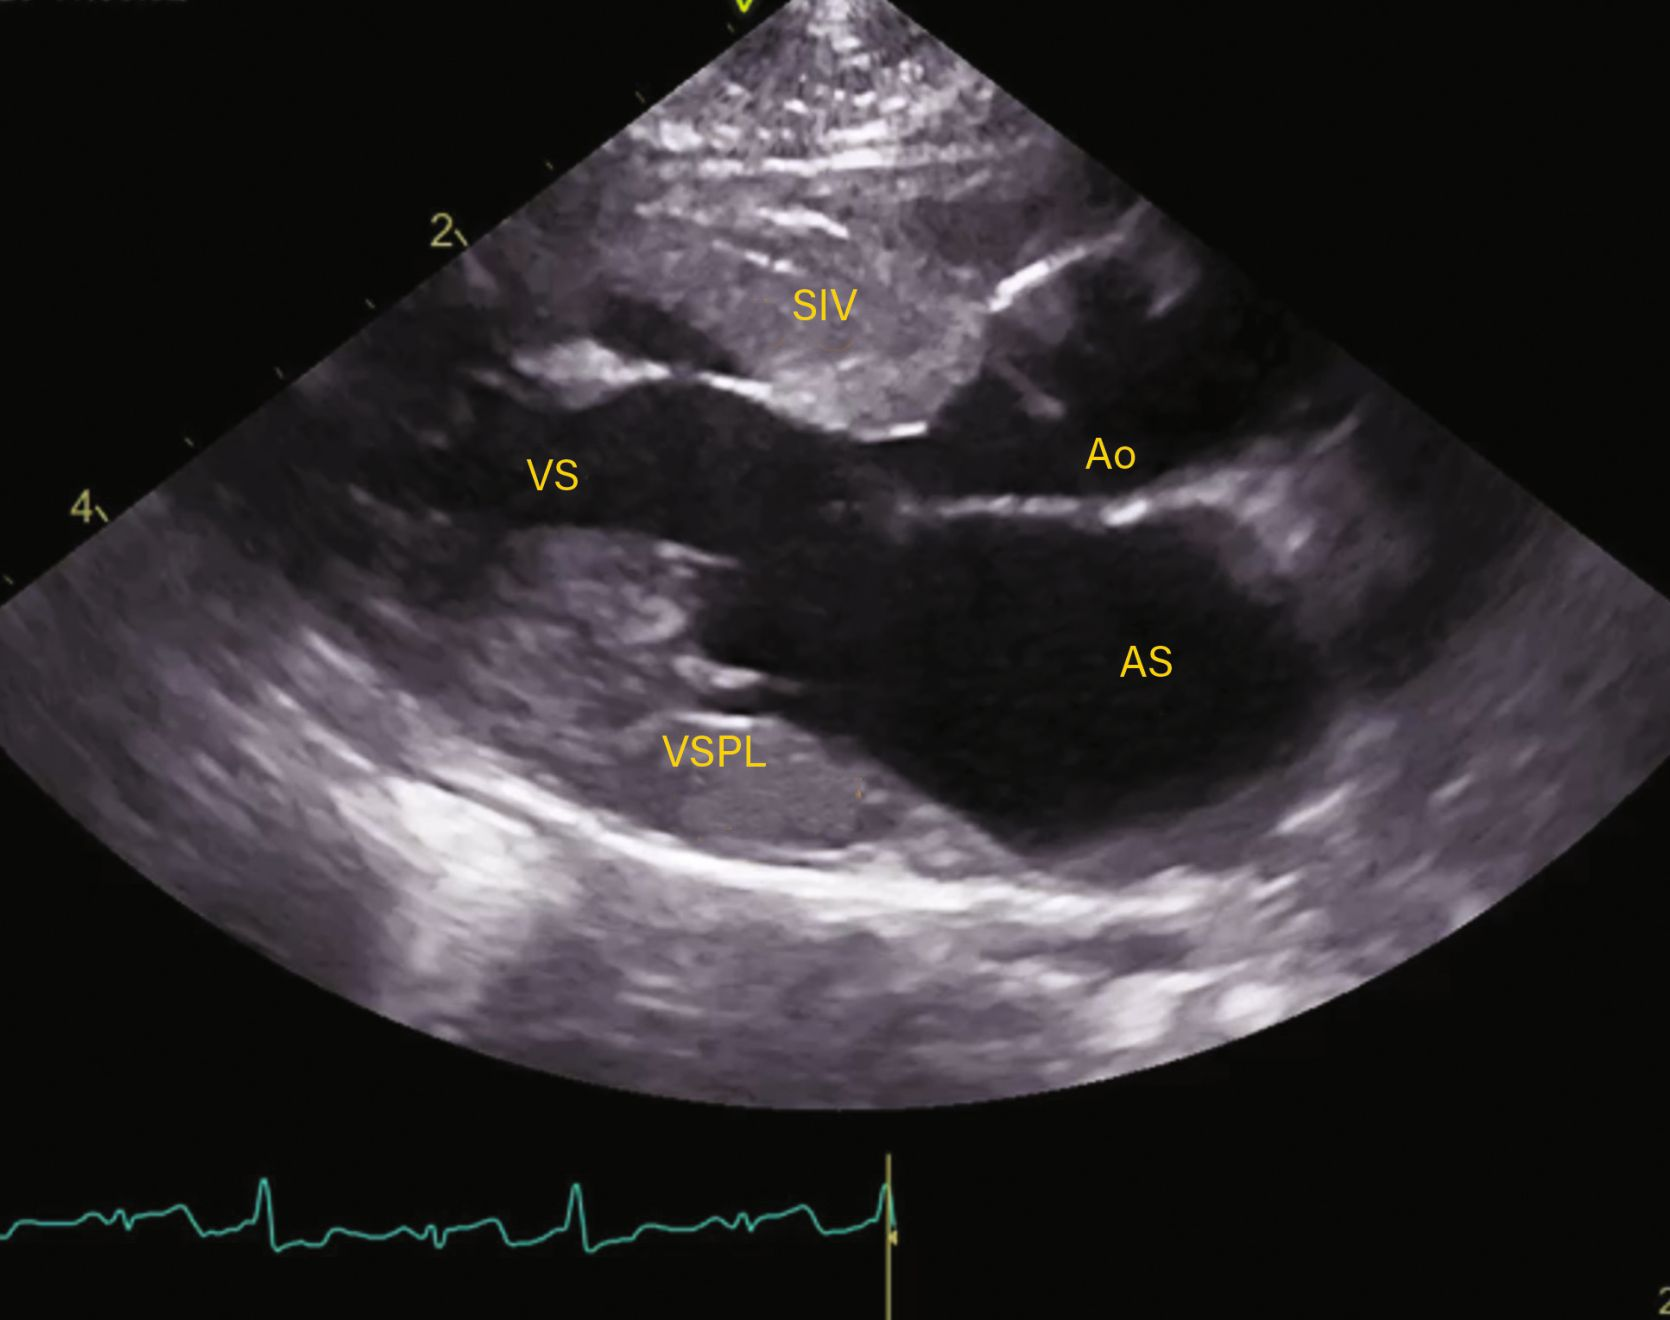

Observațiile ecocardiografice ale HCM pot să prezinte o mare variabilitate

Figura 2b. Observațiile ecocardiografice ale HCM pot să prezinte o mare variabilitate. Vizualizare parasternală dreaptă în ax scurt la nivelul mușchilor papilari prezentând hipertrofia ventriculară stângă și a mușchilor papilari.

Credit: Catheryn Partington Joanna Dukes-McEwan

Abrevieri: LA , atriul stâng (AS); LV, ventriculul stâng (VS); Pm, mușchiul papilar

Abrevieri: Ao, aorta; IVS (SIV), sept interventricular; LA, atriul stâng (AS); LV, ventriculul stâng (VS); LVFW, peretele liber al ventriculului stâng; MV, valva mitrală (VM).